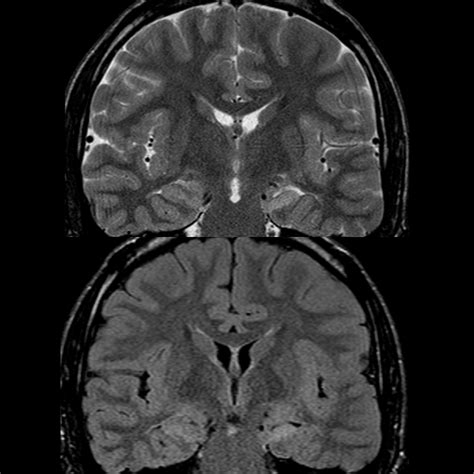

MRI (Magnetic Resonance Imaging) The "Gold Standard" to visualize hippocampal atrophy, volume loss, and increased signal intensity.

⚠️ Note: High-resolution MRI protocols, specifically designed for epilepsy (often called an epilepsy protocol MRI), are essential for detecting subtle signs of MTS that might be missed on standard clinical scans.